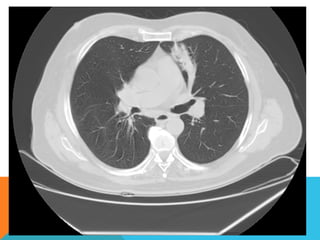

ABORDAJE TÉCNICO: Se realiza estudio con ventana mediastinal y de parénquima pulmonar con técnica de ALTA

RESOLUCION, en inspiración y espiración, mediante  cortes axiales, desde ápices hasta bases pulmonares, con las

siguientes observaciones

En las partes blandas y las estructuras óseas dentro de los límites de la normalidad. Las regiones axilares libres.

Ambos pulmones con neumatización conservada, con sobredistensión pulmonar, y áreas de atrapamiento aéreo,

bilateral con cambios fibrosos cicatriciales apicales derechos. Se demuestran áreas de condensación en topografía

predominantemente parenquimatosa pulmonar derecha, la mayor de ellas evidenciada hacia la base, acompañada

de broncograma aéreo, la medición máxima al corte axial de 6.1 por 2.2 cm, en topografía del segmento posterior

del lóbulo inferior, S10 así como también otra más se definen topografía de similares características en topografía

del segmento medial del lóbulo medio, S5. En topografía parenquimatosa pulmonar izquierda imagen de similares

características a las ya descritas en topografía del segmento lingular inferior, S4.

No hay derrame ni áreas de engrosamiento pleurales.

El patrón vascular es de características normales donde no se delimitan imágenes de lesiones aneurismáticas

únicamente cambios por aortoesclerosis incipiente.

El corazón de dimensiones conservada, de contornos regulares, sin desplazamientos; en la región hiliar derecha se

define adenopatía de medición máxima corte axial de 1.6 por 1.4 cm.

ABORDAJE TÉCNICO: Serealiza estudio con ventana mediastinal y de parénquima pulmonar con técnica de ALTA RESOLUCION, en inspiración y espiración, mediante  cortes axiales, desde ápices hasta bases pulmonares, con las siguientes observaciones En las partes blandas y las estructuras óseas dentro de los límites de la normalidad. Las regiones axilares libres. Ambos pulmones con neumatización conservada, con sobredistensión pulmonar, y áreas de atrapamiento aéreo, bilateral con cambios fibrosos cicatriciales apicales derechos. Se demuestran áreas de condensación en topografía predominantemente parenquimatosa pulmonar derecha, la mayor de ellas evidenciada hacia la base, acompañada de broncograma aéreo, la medición máxima al corte axial de 6.1 por 2.2 cm, en topografía del segmento posterior del lóbulo inferior, S10 así como también otra más se definen topografía de similares características en topografía del segmento medial del lóbulo medio, S5. En topografía parenquimatosa pulmonar izquierda imagen de similares características a las ya descritas en topografía del segmento lingular inferior, S4. No hay derrame ni áreas de engrosamiento pleurales. El patrón vascular es de características normales donde no se delimitan imágenes de lesiones aneurismáticas únicamente cambios por aortoesclerosis incipiente. El corazón de dimensiones conservada, de contornos regulares, sin desplazamientos; en la región hiliar derecha se define adenopatía de medición máxima corte axial de 1.6 por 1.4 cm.